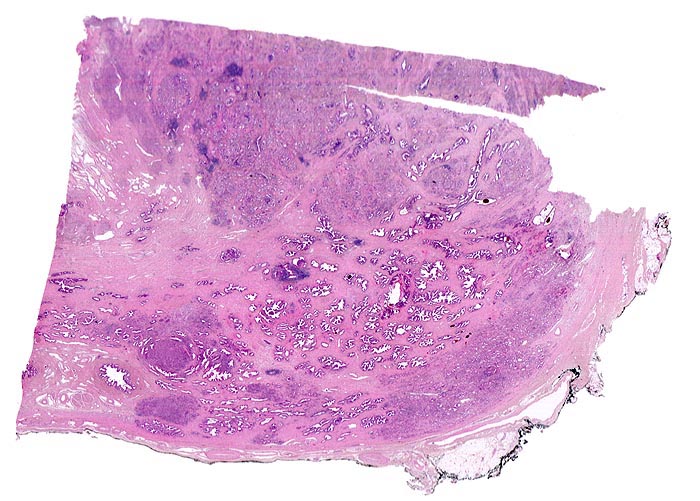

Multiple Karzinomherde infiltrieren das Prostatagewebe. Die normalen Drüsen sind deutlich grösser als die Karzinomdrüsen und enthalten in der Übersichtsvergrösserung erkennbare Lumina. Da die Karzinomdrüsen deutlich kleiner sind, erscheinen die Karzinomherde in der schwachen Vergrösserung als dunkle, unscharf begrenzte Flecken ohne erkennbare drüsige Strukturen.

Der Resektionsrand ist mit schwarzer Tusche markiert (schwarzer Streifen am Rand des Präparates).